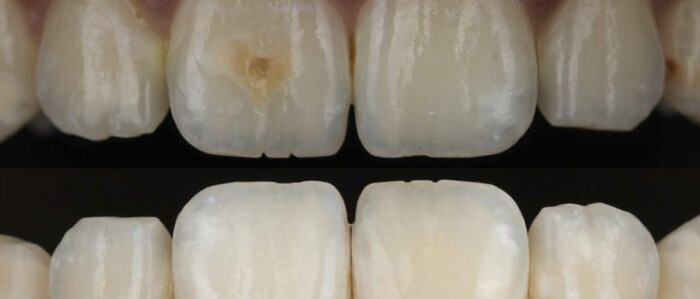

Глубокая инфильтрация смолы для консервативного лечения центрального резца, пораженного MIH

Молярно-инцизурная гипоминерализация (MIH) была впервые определена в 2001 году Weerheijm et al. как “гипоминерализация системного происхождения, проявляющаяся в виде демаркированных качественных дефектов эмали от одного до четырех первых постоянных моляров (…), часто связанных с пораженными резцами”...